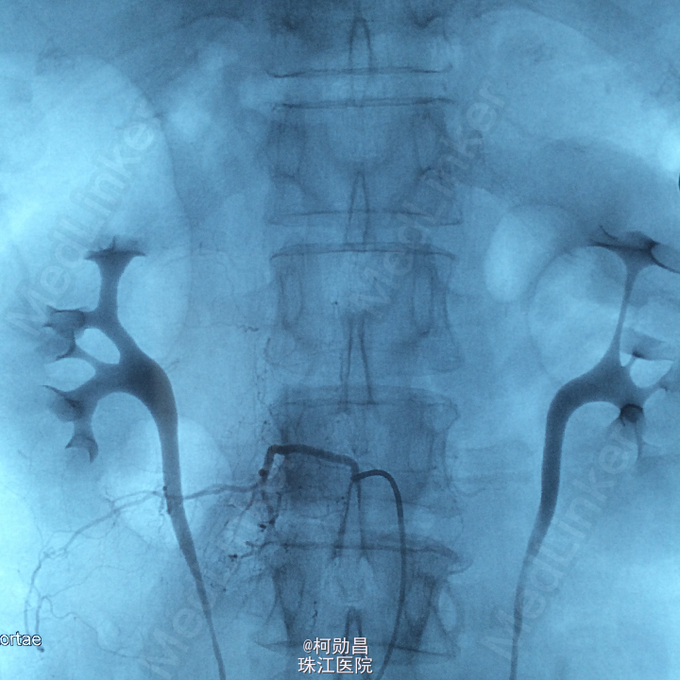

诊断:硬脊膜动静脉瘘 处理:予全麻下行栓塞治疗,选择予 withn-butyle-2-cyanoacrylate(医用胶)完全闭塞 。

9 个月后随访 MRI 可见脊髓内的异常信号影及强化血管影信号减低。患者预后较好。